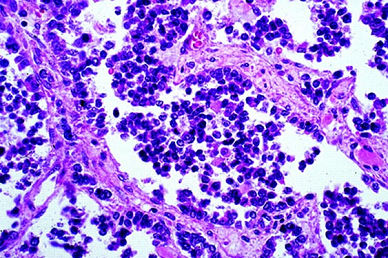

Soft Tissues: Alveolar Rhabdomyosarcoma

Alveolar Rhabdomyosarcoma, Magnification 20. Dyshesive And Infiltrative

rhabdomyosarcoma alveolar infiltrative magnification

Webpathology.com: A Collection Of Surgical Pathology Images

rhabdomyosarcoma alveolar webpathology pathology

Webpathology.com: A Collection Of Surgical Pathology Images

rhabdomyosarcoma alveolar webpathology pathology comments microscopic

Webpathology.com: A Collection Of Surgical Pathology Images

rhabdomyosarcoma webpathology

Webpathology.com: A Collection Of Surgical Pathology Images

rhabdomyosarcoma alveolar webpathology